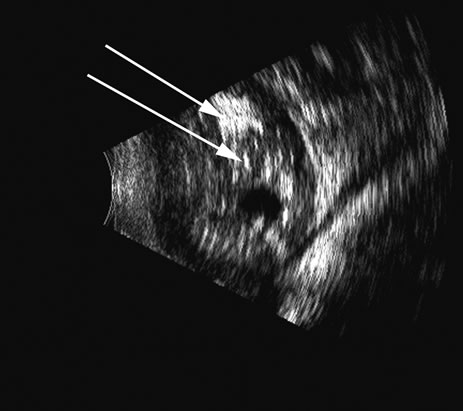

Fig. 13. A long-standing retinal detachment exhibits a characteristic truncated cone pattern, with the apex of the cone attached at the optic nerve. Folds of the retina can be seen as cyst-like protrusions on the retina surface (arrows).

The retina is a highly reflective surface (specular reflector) and can be seen to always maintain its connection to the optic nerve, even when drawn into an organized detachment. It may not be attached at the ora serrata in giant tears, but otherwise it generally maintains the two “landmark” attachments of optic nerve and ora serrata (Fig. 13), which can aid in differentiating the retina from the PLM of the retracted vitreous and from the choroid, in which the detachment may extend anterior to the ora and rarely extend back behind the vortex veins to the nerve (Fig. 14).14